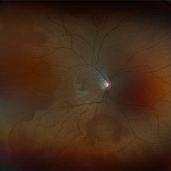

Sickle Cell Retinopathy (11 files)

Sickle Cell Retinopathy (11 files)

Sickle Cell Retinopathy SC (6 files)

Sickle Cell Retinopathy SC (6 files)

Sickle Cell (1 file)